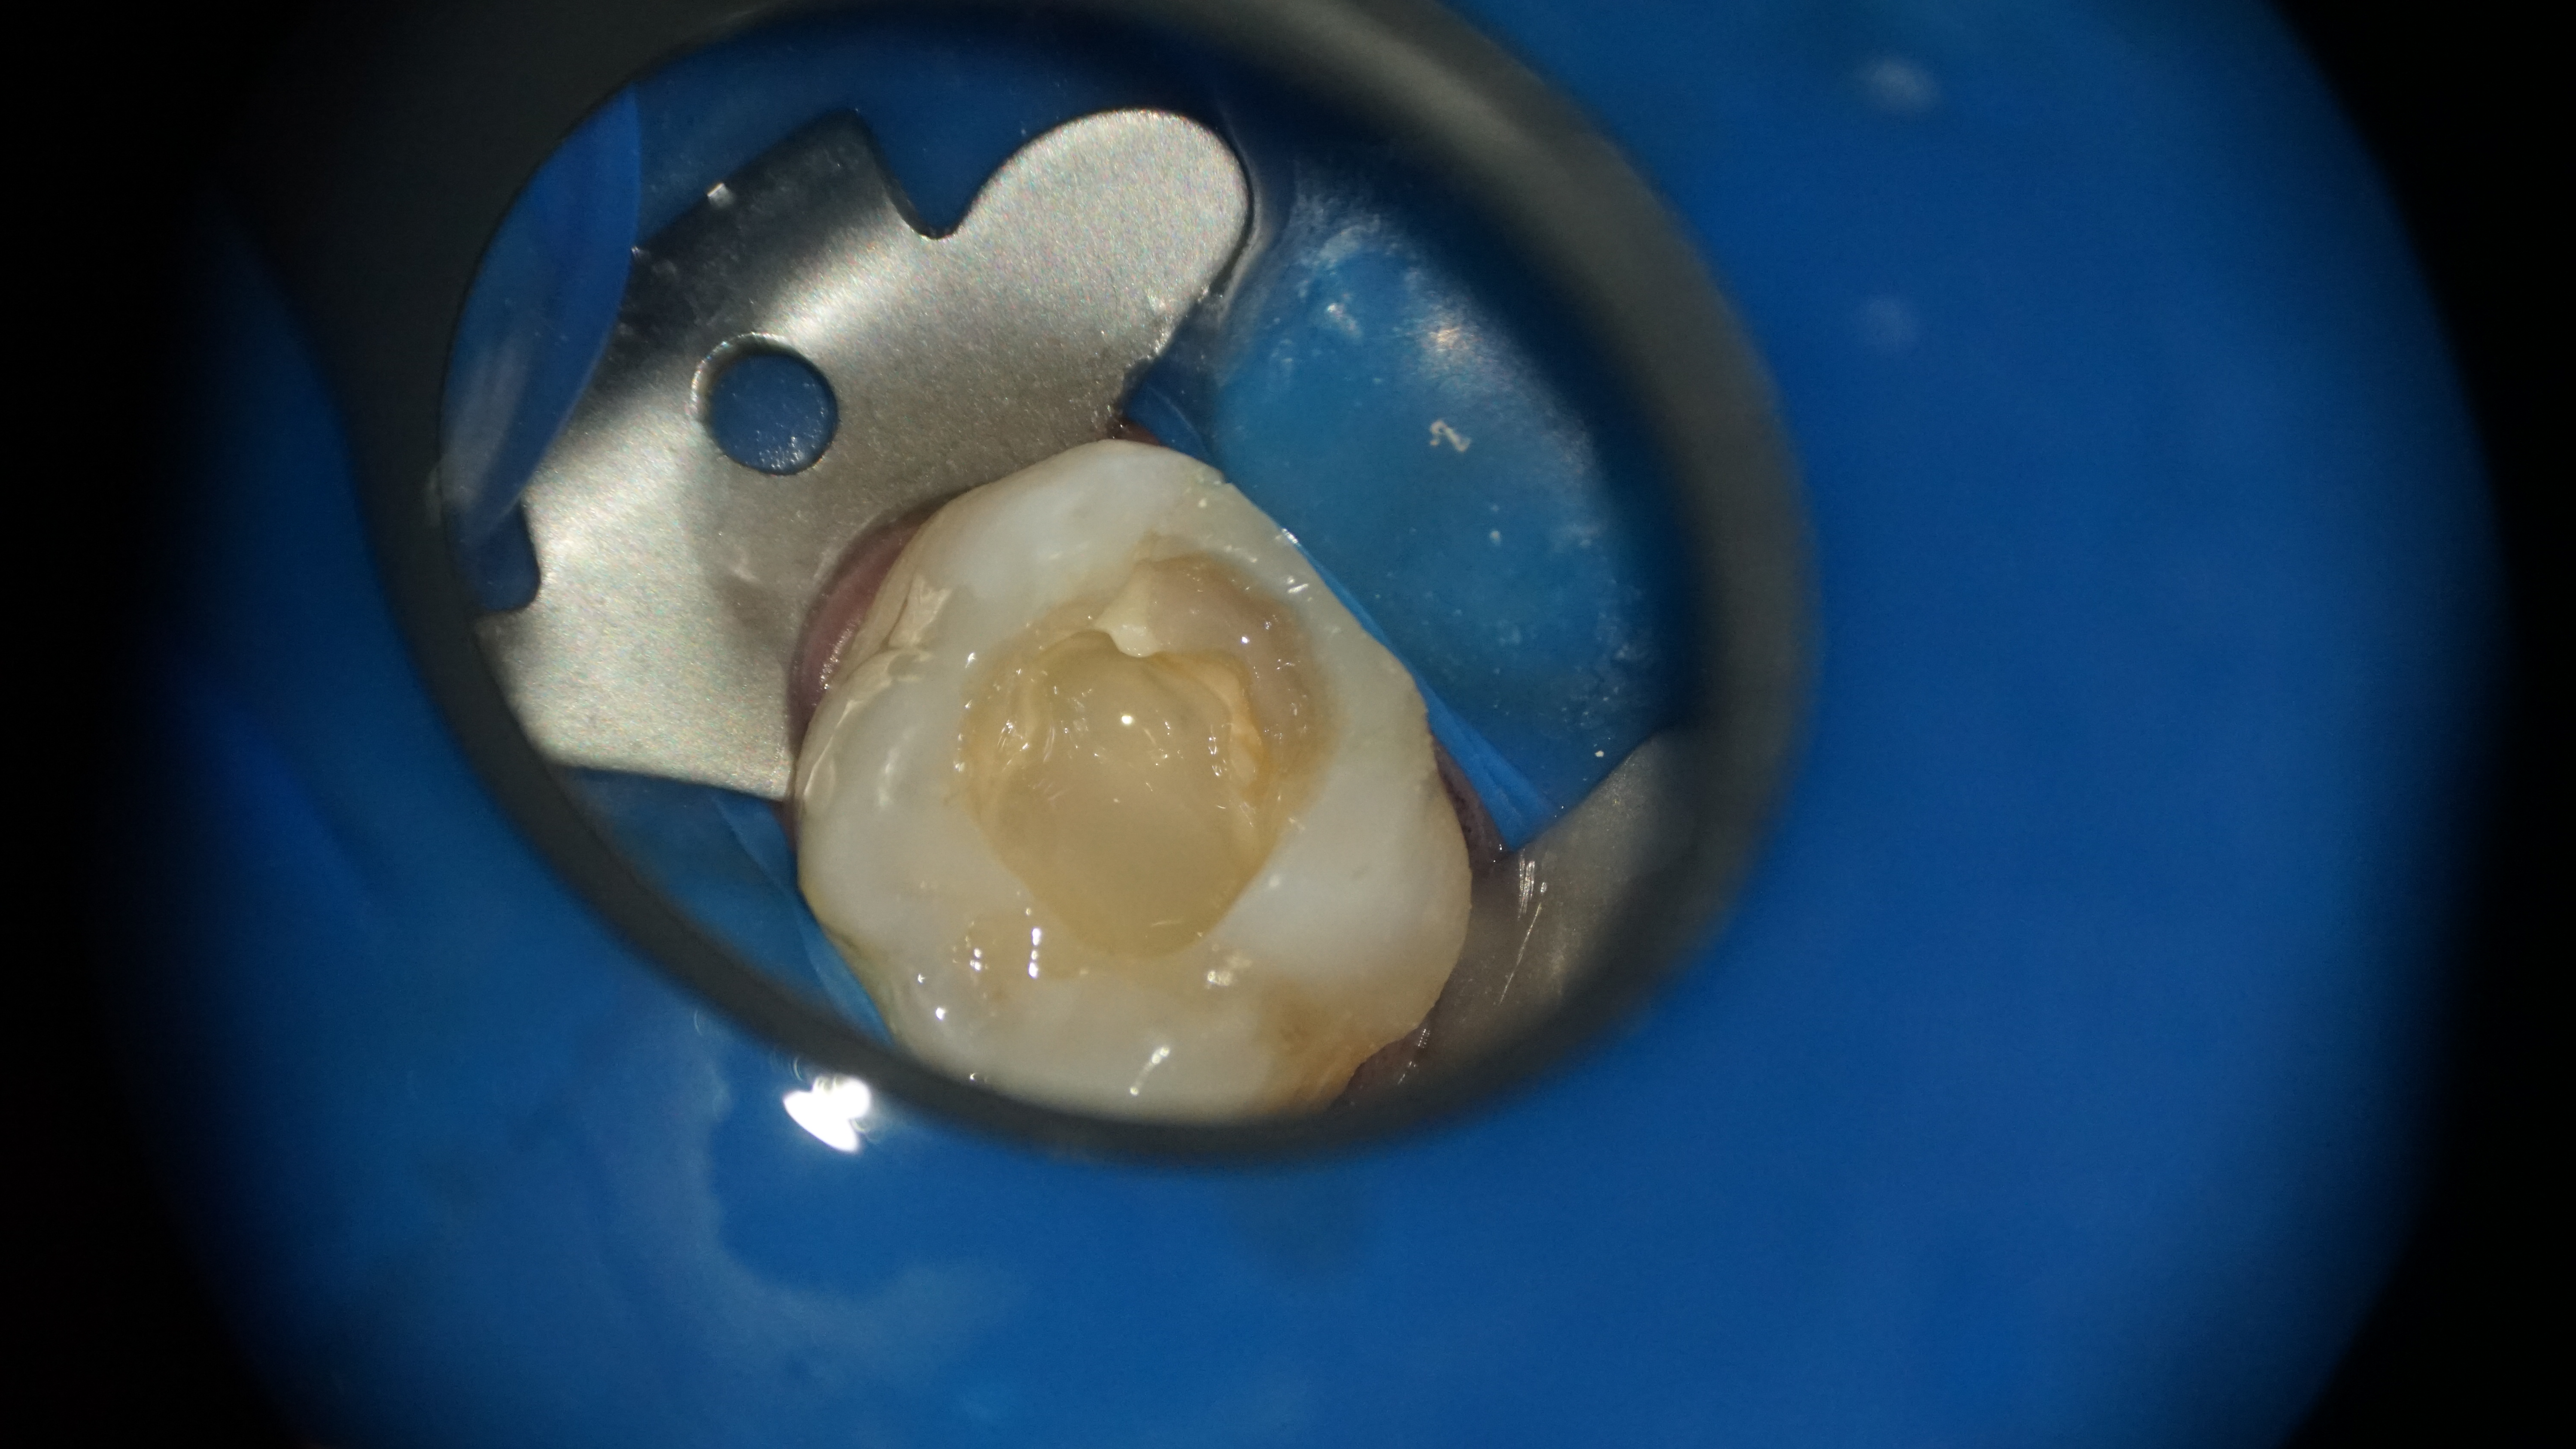

Înaintea tratării efective a canalelor radiculare, a fost necesară închiderea perforației cu un material bioceramic și îndepărtarea fragmentului fracturat prin vibrație ultrasonica (Figura 3). Succesul acestor proceduri reprezinta o parte crucială a tratamentului asigurand integritatea structurală a dintelui și a evitat complicațiile ulterioare. (Figura 4 + Figura 5)

Figura 3. Închiderea perforației cu un material bioceramic și îndepărtarea fragmentului fracturat prin vibrație ultrasonică